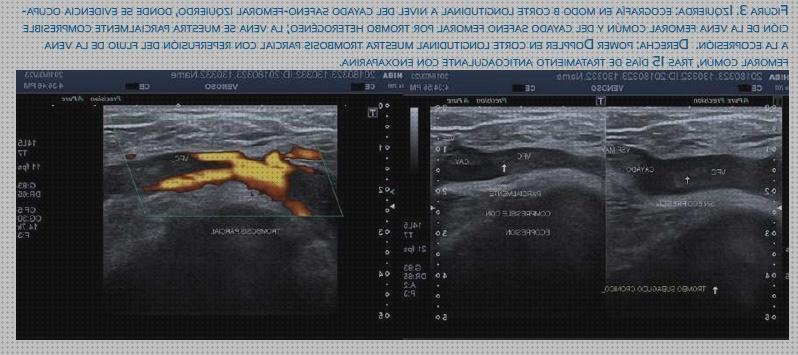

Científicos canadienses hallaron que aunque ninguna evidencia tiene una sensibilidad al cien%, la realización de ultrasonografías seriadas a lo largo de 7 días con técnico doppler en el vena iliaca excluye el diagnóstico de trombosis venosa profunda en mujeres embarazadas sintomáticas.